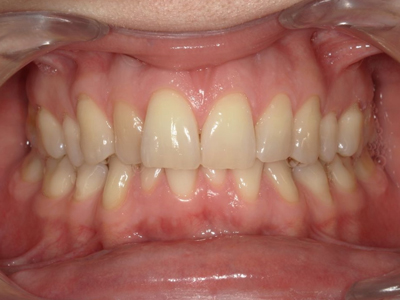

Après traitement orthodontique et réalisation d’une attelle fibrée (courtoisie Dr Patrick Fournier)